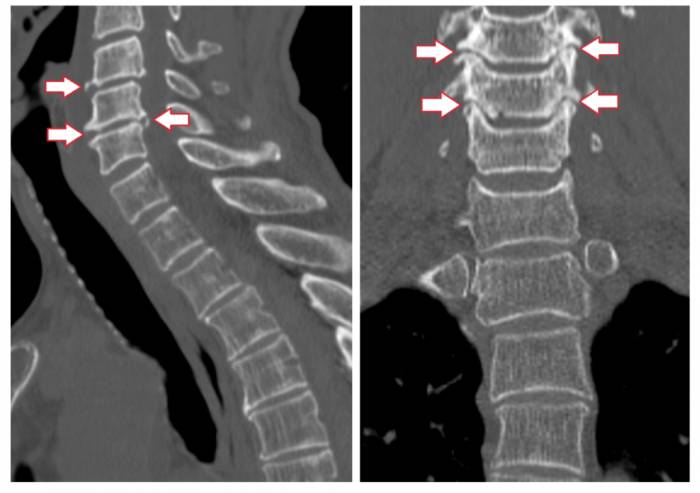

КТ. Компьютерная томография позволяет провести детальный анализ костных и мышечных тканей, а также кровеносных сосудов. Наиболее информативной считается спиральная КТ, которая помогает обнаружить даже незначительные дегенеративно-дистрофические изменения.

Если на снимках КТ, МРТ или рентгенограмме обнаруживаются патологические изменения, вертебролог ставит диагноз унковертебральный артроз. Степень выраженности этих изменений позволяет врачу определить стадию болезни и назначить наиболее подходящее лечение.